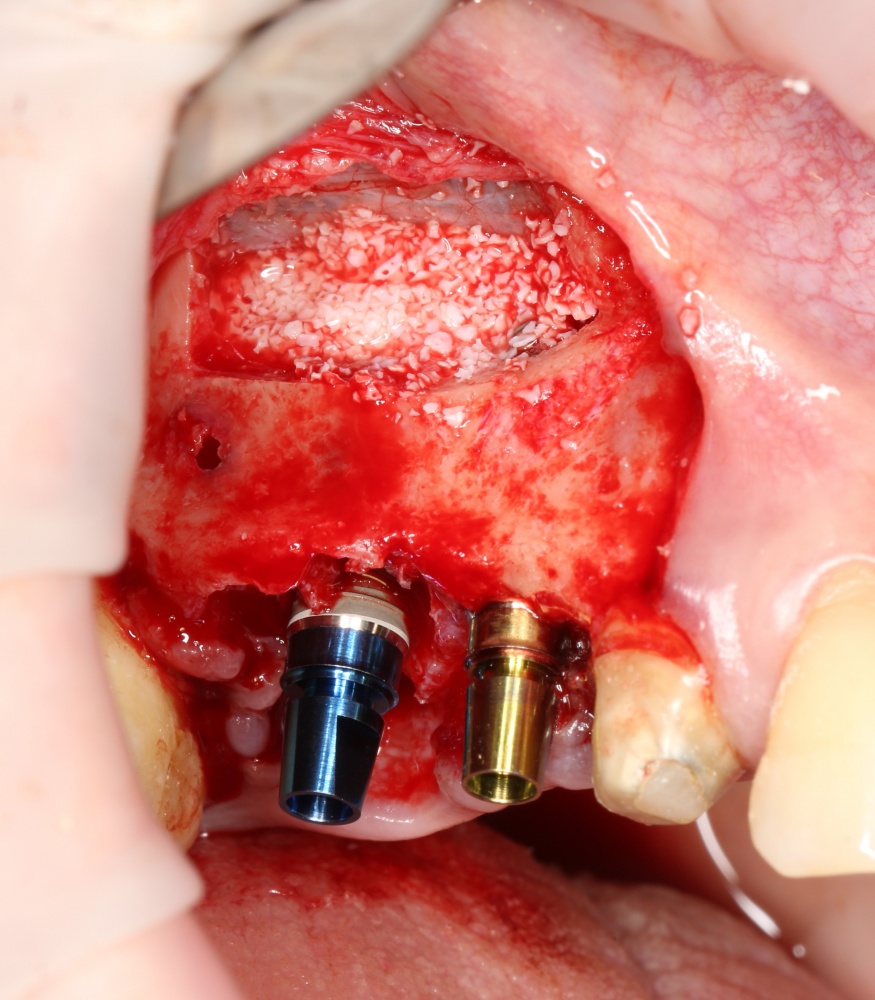

Напомню, что для этой работы я выбрал субкрестальные имплантаты Ankylos C/X. Они прекрасно сочетаются с любым методом остеопластики.

Я не планирую установку супраструктур или коронок, поэтому на уровень первичной стабильности можно положить болт. Даже наоборот — чем меньше крутящий момент при установке, тем лучше. Для имплантатов Ankylos и подобных им, это особенно важно. В общем, момент силы при установке — не более 10-15 Нсм.

Ремарка: имплантаты с предустановленными имплантодержателями хороши тем, что с ними легко контролировать позиционирование имплантатов. В случае с Ankylos С/Х - еще и крутящий момент. Имплантодержатель должен отсоединяться от имплантата с легким щелчком. Если его клинит, и тебе приходится прикладывать для этого усилия, то ты, однозначно, превысил момент силы во время установки имплантата. Следовательно, жди проблем.

Глянем на то, что получилось:

Осталось адаптировать костный блок (убрать острые края), проверить его фиксацию и, при необходимости, добавить винты. Десятисекундное дело.